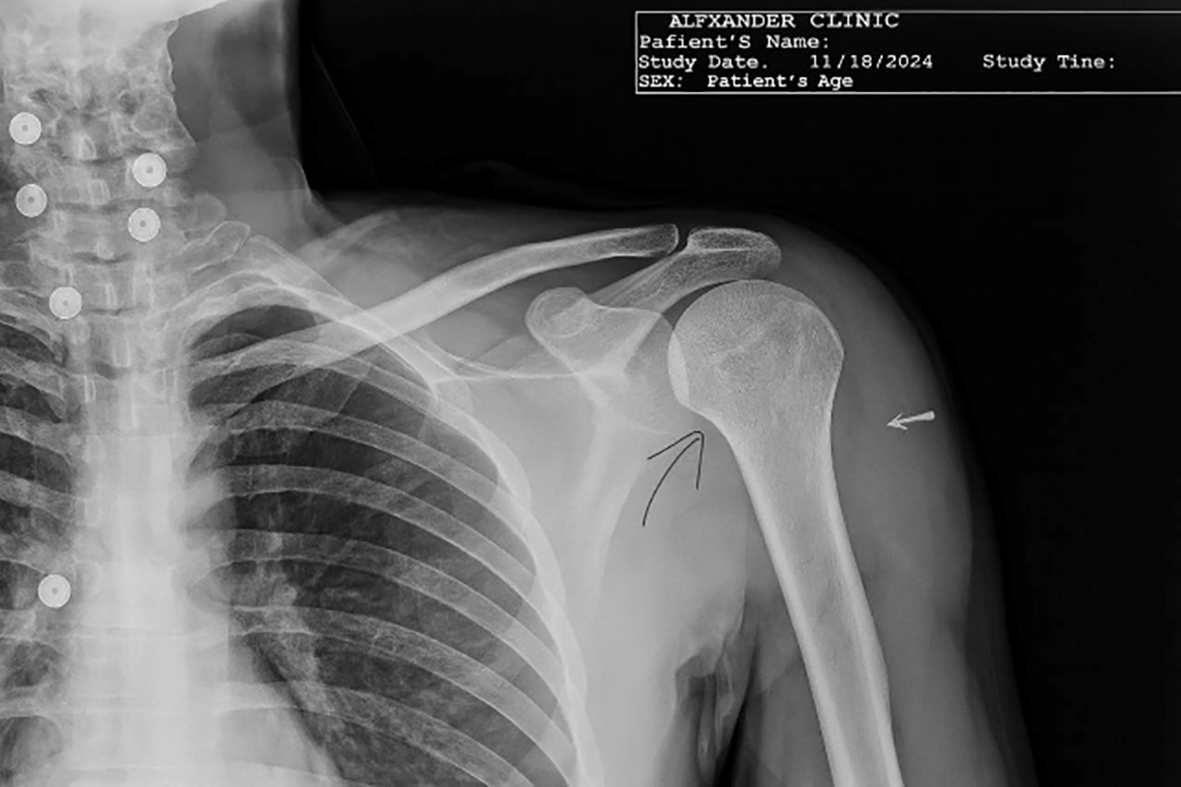

On examination, there was loss of shoulder contour with limitation of movement with a positive posterior drawer test. Radiographs showed a light-bulb appearance ( Figure 1). The CT scan showed Reverse Hillsach lesion ( Figure 2).

On examination, there was loss of external rotation movement of the shoulder. The X-rays showed a light-bulb appearance ( Figure 5). The CT scan: shows Reverse Hillsach lesion ( Figure 6).

The patient was sent for X-rays that showed a light-bulb appearance ( Figure 9). The CT scan showed the impaction of the Humeral Head in the glenoid fossa with an internally rotated Humeral Head that locks the head in situ (inside the glenoid fossa) without exiting the humeral head outside the glenoid socket ( Figure 10).

Radiology included AP, lateral, and axillary views. Computed tomography (CT) scans are required in doubtful cases. Radiological signs included a light bulb appearance, empty glenoid sign (anteroposterior, AP view), or indentation of the anterior part of the humeral head (in Lateral or Axillary view).